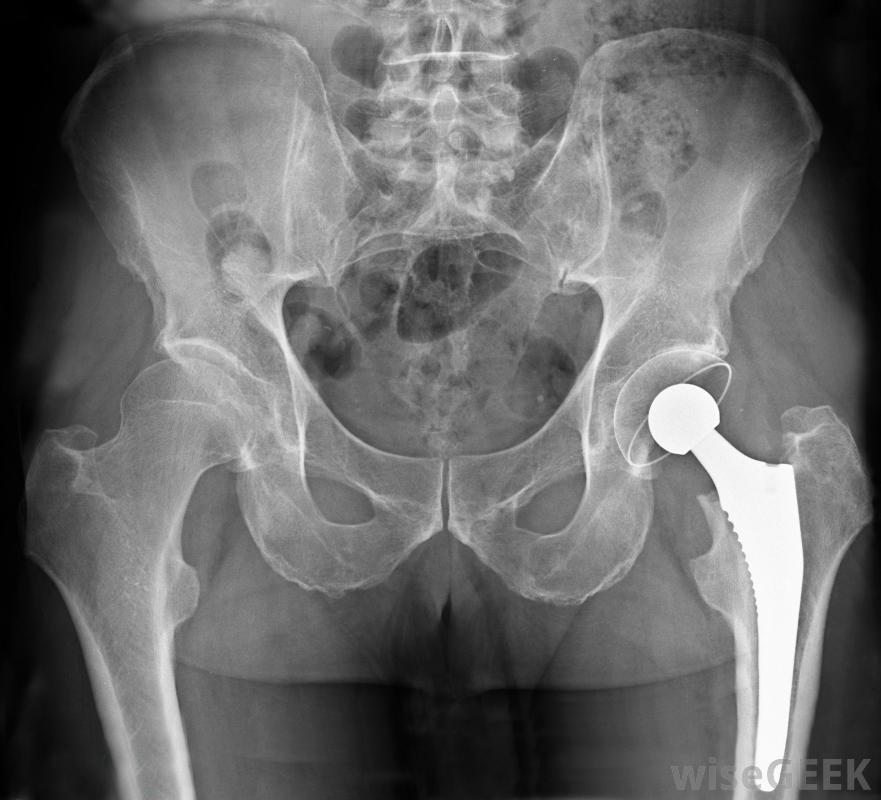

股骨是人體中最長、最厚、最結實的骨頭。它從骨盆一直延伸到膝蓋的頂部,在一個中等身材的人身上通常有20英寸(50厘米)長。更準確地說是股骨,這是人體解剖學的重要組成部分,為整個上半身提供支撐,并確保能量向下分配到足部。骨骼是大多數髖部骨折的部位,因此通常是髖關節置換手術中的主要骨骼之一股骨骨折在足球等高接觸運動中很常見。股骨是人體抵抗重力的幾種骨骼之一,起著至關重要的作用在站立、行走、跑步和跳躍時,它的形狀像一個空心的圓柱體,給它提供了承受巨大壓力和承受沉重重量所必需的力量。骨頭的頭部像一個球,嵌在骨盆的一個叫做髖臼的深窩里。將頭部連接到較薄的骨干部分是股骨頸。就在脖子下面,外側有一個腫塊叫做大轉子,臀部的大肌肉附著在腫塊處的股骨上。在髖關節置換手術中,股骨頂部是用假肢代替股骨骨折通常發生在骨頭的頸部。在年輕人中,骨折通常是由于嚴重的跌倒、打擊、運動損傷,或者交通事故。老年人的病因可能是骨質疏松癥,骨質疏松癥會加速骨質疏松癥。老年人有時也會在頸部略低于股骨粗隆間的區域發生股骨骨折。無論是年輕人還是老年人,股骨骨折通常都會發生通常被認為是嚴重損傷的髖部骨折。骨折的愈合需要三到六個月。股骨骨折通常需要廣泛的物理治療才能恢復活動能力股骨骨折的危險因素通常包括參加高接觸運動,如足球或曲棍球,衰老,骨質疏松癥的發病,肌肉質量減少,以及患有癌癥等經常侵襲骨骼的疾病有幾種預防措施可以預防股骨骨折,包括避免涉及重大撞擊的高風險活動,保持活躍以保持敏捷,鍛煉身體以增強肌肉力量以減少摔倒的可能性,吃高鈣和維生素D的食物,駕駛或乘坐汽車時系安全帶參加體育運動或其他體育活動時,應穿戴適當的防護裝備和襯墊物理療法可能對因肌肉喪失或骨質疏松而股骨虛弱的人非常有用。股骨螺旋骨折在老年人中很常見亞裔美國婦女患骨質疏松癥的風險很高患骨質疏松癥的風險尤其大。股骨從骨盆延伸到膝蓋頂部。